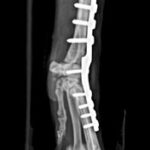

Luxación vertebral, tratada con implantes múltiples y cemento óseo.